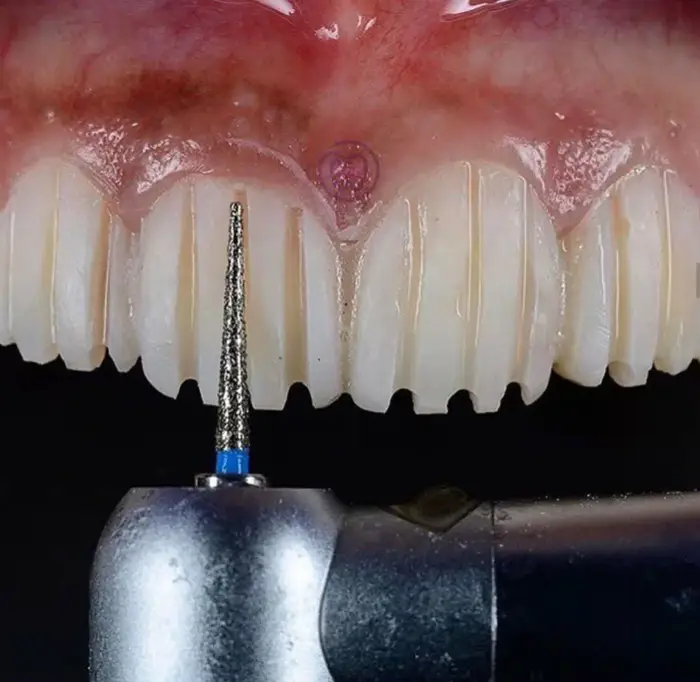

#2 Krátka ukážka toho, ako sa pripravujú zuby na nasadenie zubnej fazety.